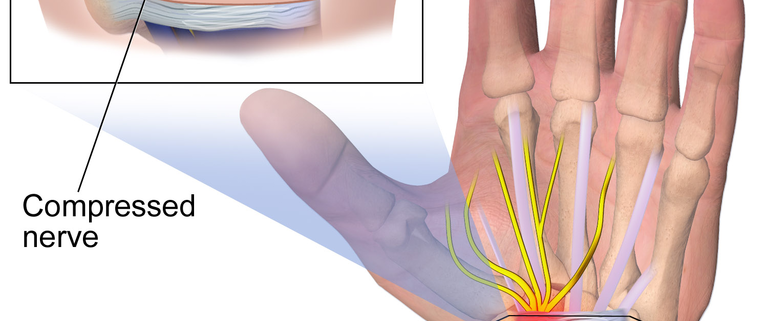

Carpal tunnel syndrome (CTS) is a common condition that affects people from all walks of life. This condition affects the hand and arm, causing tingling, numbness, and pain. It’s caused by pressure on the major nerve that travels through the wrist, known as the median nerve. Recent statistics show that up to 5% of adults may be affected by CTS, with women being affected three times more often than men.

CTS is often caused by conditions or activities that put pressure on the median nerve at the wrist. These can include:

- Surgery: If symptoms are severe or worsening, or if non-surgical treatments have not helped, your doctor may recommend surgery to relieve pressure on the median nerve.